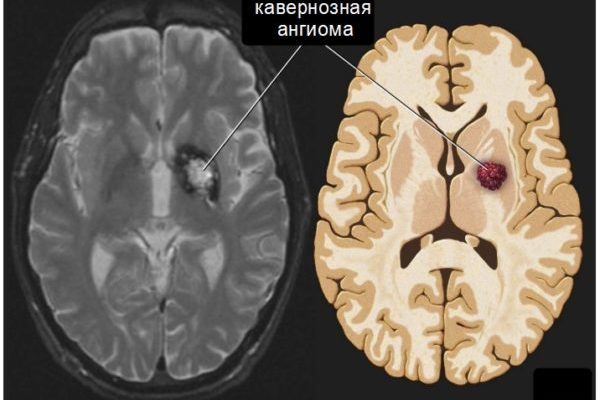

Кавернозная ангиома

В основе этой страшной патологии лежат сосудистые полости, называемые полостями. Кавернозная гемангиома головного мозга — крайне опасный недуг. Стены кавернозных пород разделены не слишком прочными тонкими перемычками. Образование может лопнуть, что приведет к кровоизлиянию в мозг и смерти.

Специфические кавернозные клетки наполнены кровью и иногда достигают внушительных размеров. Осложнения возникают из-за хрупкости стенок кровеносных сосудов, что может привести к кровоизлиянию в мозг.